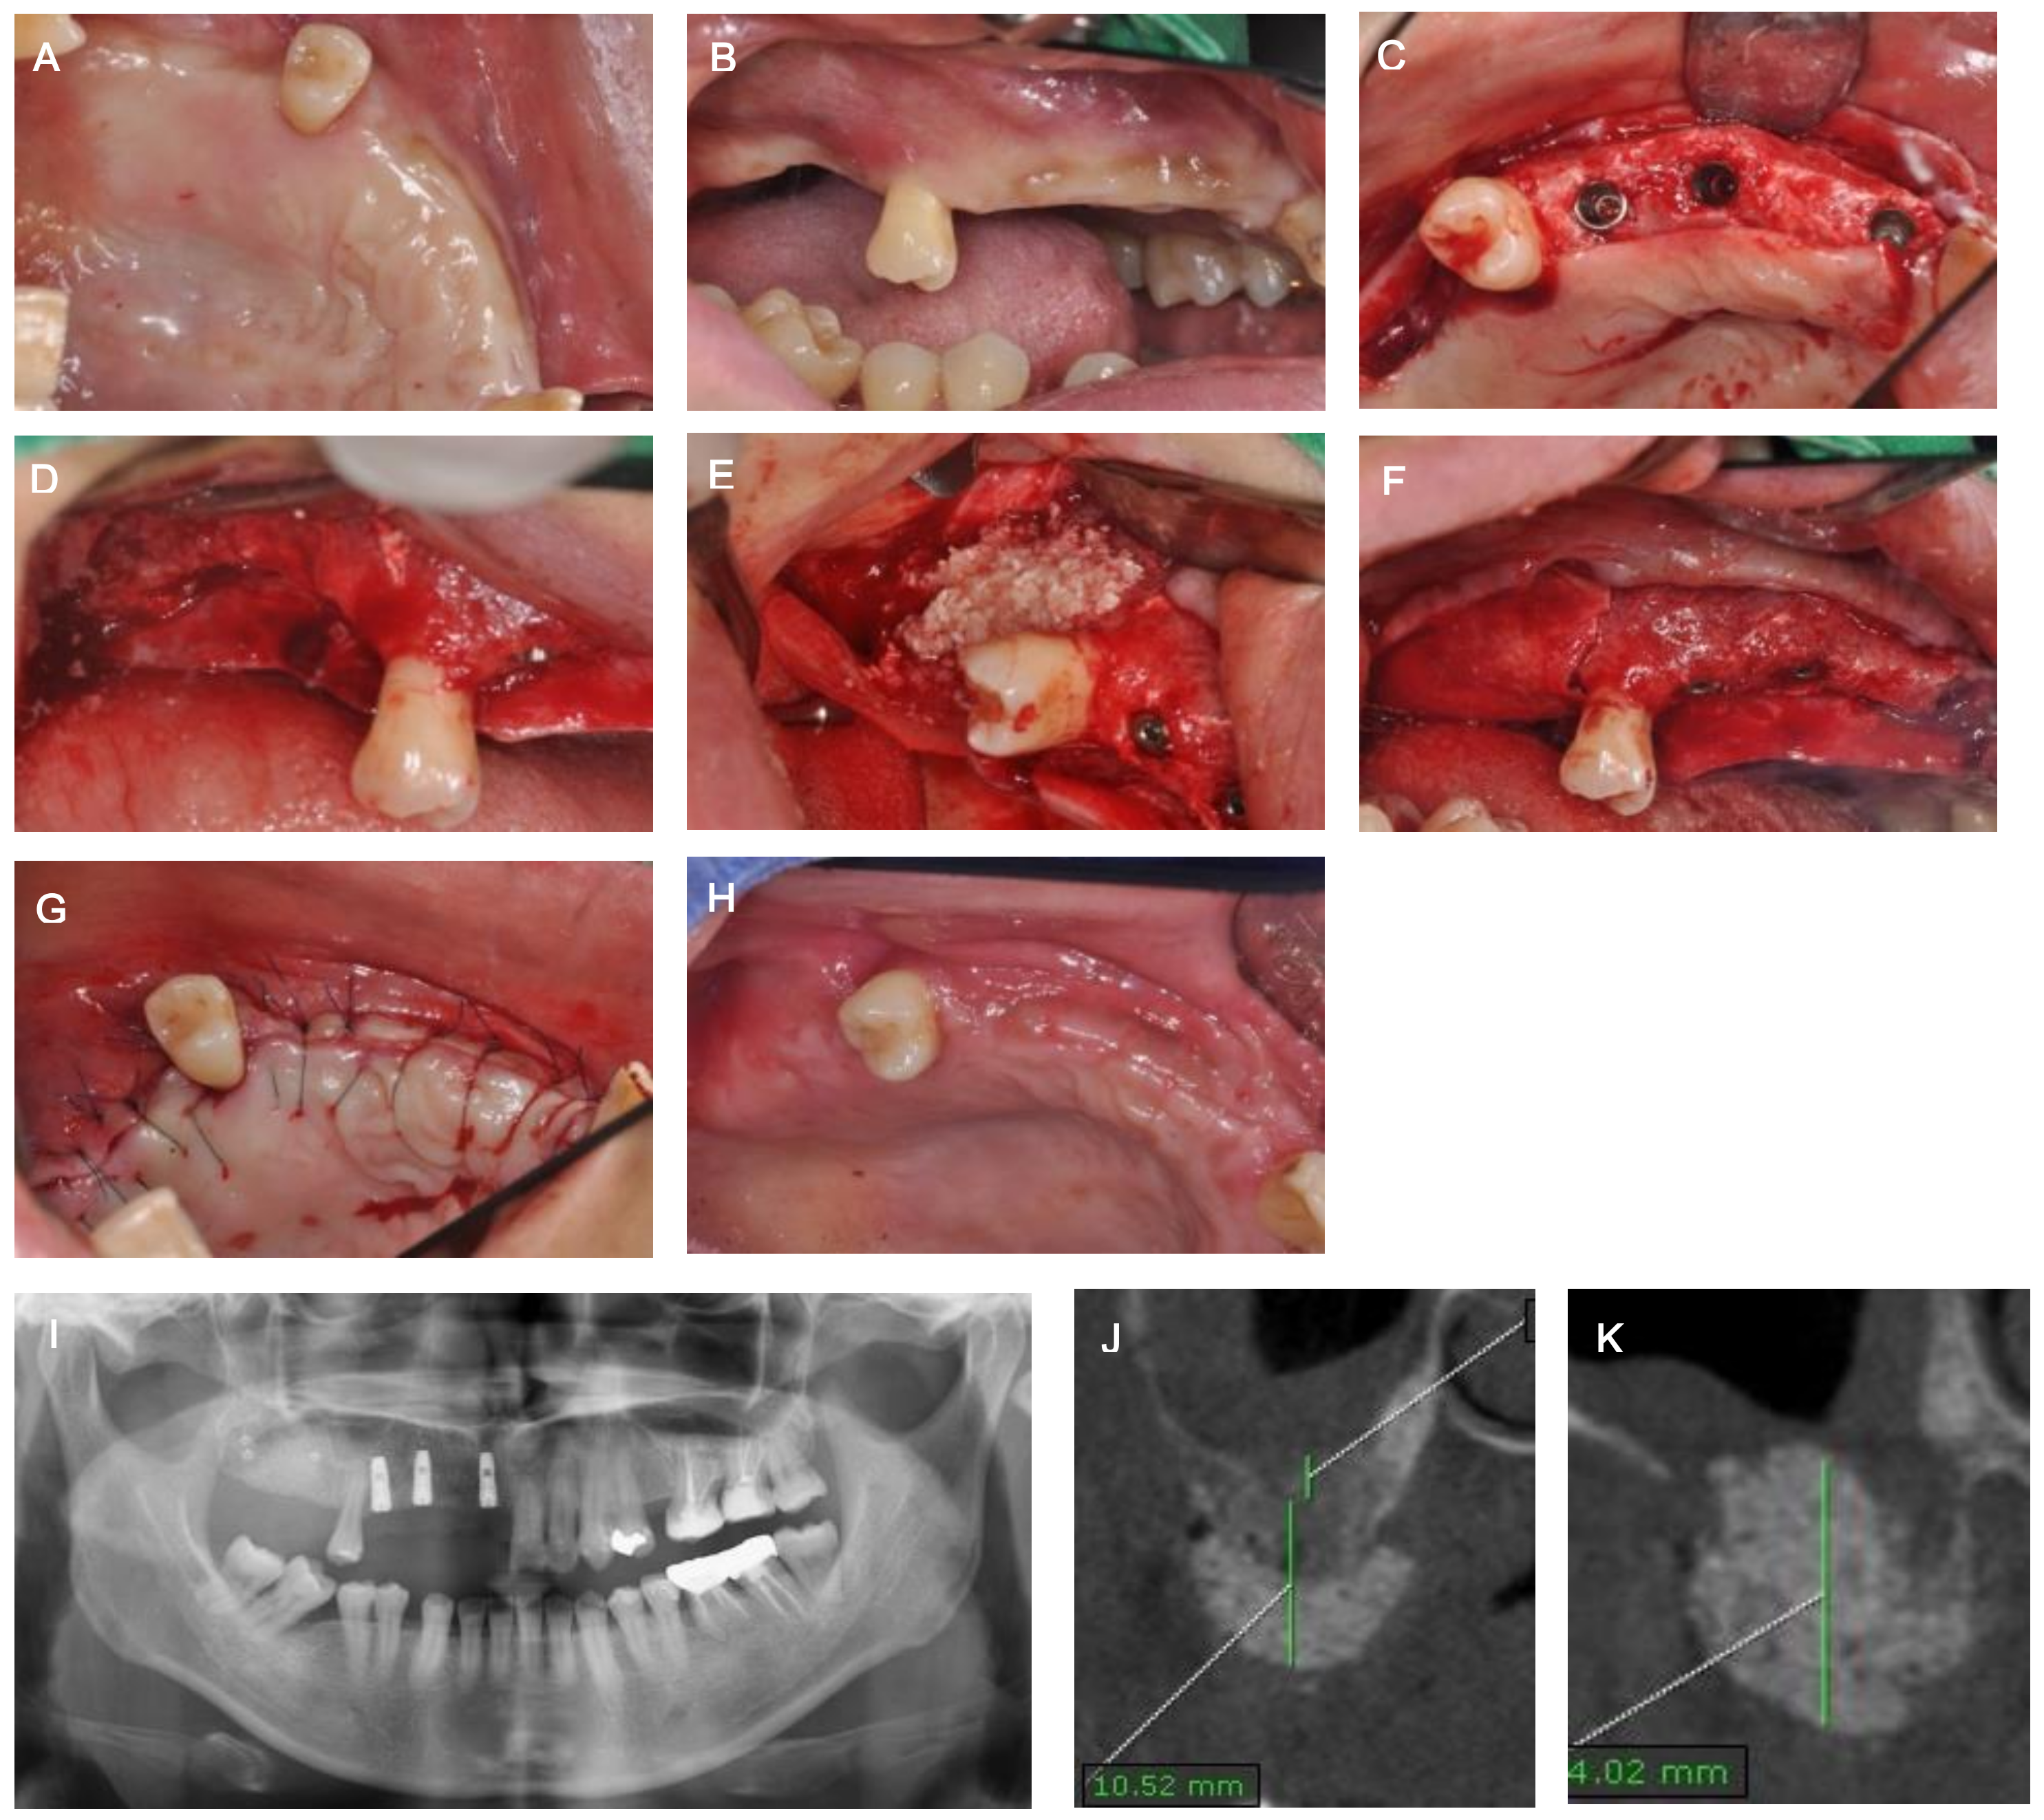

2. Case Description